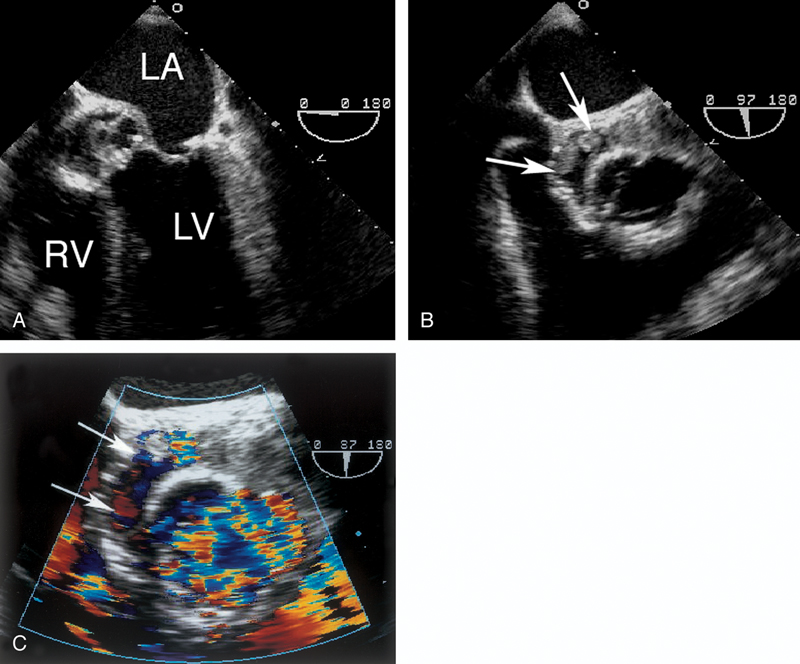

فحوصات تشخيصية لبعض امراض القلب والشرايين التاجية